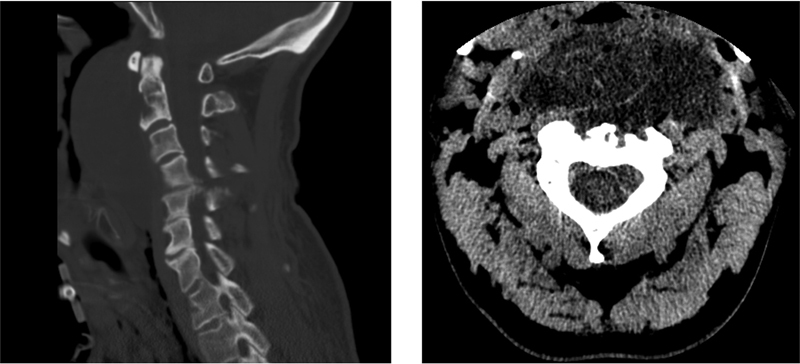

背景:脊索瘤是组织学上良性但局部侵袭性的肿瘤,易复发。我们的病例强调了在接受脊索瘤切除术的患者中长期警惕的重要性。病例报告我们报告一例47岁男性颈脊索瘤患者,在左侧锁骨上区、右侧二头肌近端和左侧下颌下区发生多发性肌肉骨骼异位复发,原发肿瘤部位无复发。原发性肿瘤切除是通过手术、辅助放射治疗和伊马替尼的联合治疗实现的。所有复发均成功切除,病理证实为异位脊索瘤。宫颈脊索瘤异位复发是罕见的,肺是最常见的远处扩散部位。骨骼肌脊索瘤复发尤其罕见,文献中仅报道了10例。脊索瘤患者远处转移的一种可能的机制表明,肿瘤细胞通过细胞因子释放、血管舒张和切除过程中引起的微创伤的结合而逃离手术道。结论颈椎脊索瘤伴骨骼肌异位复发的文献尚未见报道。颅底外科医生在没有局部复发的情况下,应注意脊索瘤异位复发的现象。

Background  Chordomas are histologically benign but locally aggressive tumors with a high propensity to recur. Our case highlights the importance of long-term vigilance in patients who have undergone chordoma resection. Case Report  We report the case of a 47-year-old man with a cervical chordoma who developed multiple musculoskeletal ectopic recurrences in the left supraclavicular region, the proximal right bicep, and the left submandibular region without recurrence in the primary tumor site. Primary tumor resection was achieved via a combination of surgery, adjuvant radiation therapy, and imatinib. All recurrences were successfully resected and confirmed via pathology to be ectopic chordoma. Discussion  Ectopic recurrence of cervical chordoma is rare and lung is the most common site of distant spread. Chordoma recurrence in skeletal muscle is particularly rare, with only 10 cases described in the literature. A plausible mechanism of distant metastatic disease in chordoma patients suggests that tumor cells escape the surgical tract via a combination of cytokine release, vasodilation, and microtrauma induced during resection. Conclusion  Cervical chordoma with ectopic recurrence in skeletal muscle has not been previously described in the literature. Skull base surgeons should be aware of the phenomenon of chordoma ectopic recurrence in the absence of local recurrence.